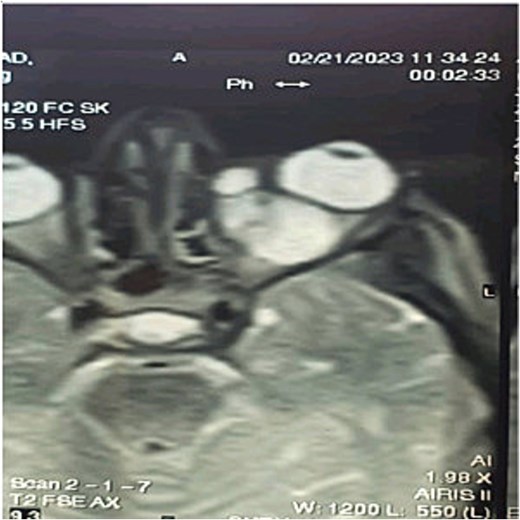

Axial, sagittal, and coronal magnetic resonance imaging (MRI) images revealed a cystic lobed lesion in the retro-ocular space measuring (25 × 16 × 18) mm and compressing the left optic nerve which was normal in diameter and magnetic signal and also compressing the eyeball to the anterior (Figs 2 and 3). The mass indicated a liquid homogenous signal without any peripheral enhancement after injection of the opaque substance. There were no other pathologies shown by the MRI. laboratory studies revealed a positive test for echinococcus granulosus antibodies at dilution 1/200.

Magnetic resonance cystic lesion images showing cystic lesion in the left orbit.